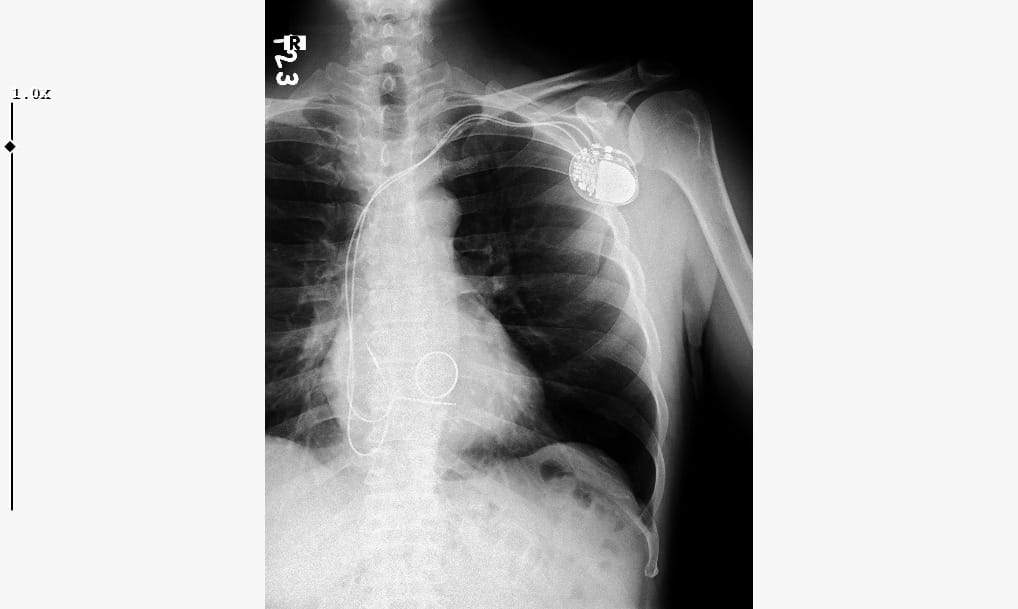

PİLİN KAYDIĞI RÖNTGENDE GÖRÜNTÜLENDİYaşanan yoğun ağrı sırasındaki ani kas hareketleri sonucunda göğse yerleştirilmiş kalp pilinin normal konumundan kayarak sol omuz bölgesine doğru yer değiştirdiği belirlendi.

Bildik'in bu gelişmenin ardından sol kolunu hareket ettirmekte zorlandığı, günlük yaşam aktivitelerini yerine getiremez hale geldiği belirtildi. Durum, röntgen görüntüleriyle de desteklendi. Görüntülerde kalp piline bağlı ince tellerin anormal biçimde kıvrıldığına ve pilin omuz bölgesine yerleştiğine dikkat çekildi.